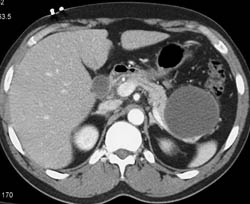

Pancreatic Cancer Encases the Celiac and SMA